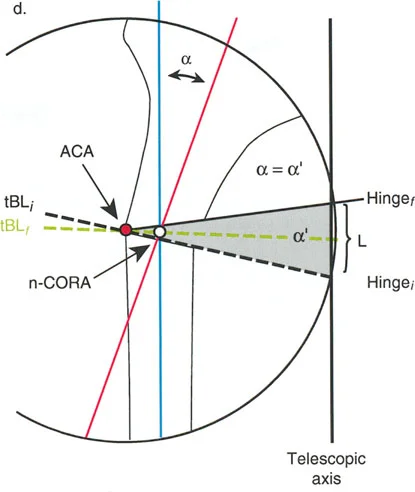

العلاج المتقدم لتصحيح تشوهات العظام بتقنيات بالي

يُعد علاج تشوهات العظام بتقنيات بالي المتقدمة نهجًا ثوريًا يجمع بين البيولوجيا والهندسة لاستعادة المحاذاة الطبيعية للأطراف وإطالة العظام. يعتمد هذا العلاج على مبدأ "توليد العظم بالشد" الذي اكتشفه إليزاروف، والذي يسمح للعظم الجديد بالنمو تدريجيًا تحت تأثير الشد الميكانيكي.

المبدأ البيولوجي: توليد العظم بالشد (Distraction Osteogenesis)

قبل الخوض في تفاصيل الأجهزة الميكانيكية، من الضروري فهم الركيزة البيولوجية التي نتعامل معها. اكتشف إليزاروف أن الأنسجة الحية، عندما تتعرض لشد بطيء وثابت، تصبح نشطة أيضيًا. هذا "تأثير الشد والضغط" يحفز تكوين العظم (osteogenesis)، وتكوين الأوعية الدموية (angiogenesis)، وتكوين الأنسجة الأخرى (histogenesis) مثل العضلات والأعصاب والجلد.

ومع ذلك، تعتمد هذه "المعجزة البيولوجية" بشكل كبير على الاستقرار الميكانيكي. إذا كان المثبت الخارجي شديد الصلابة، فقد لا يتكون العظم الجديد بشكل كافٍ؛ وإذا كان فضفاضًا جدًا، فإن قوى القص ستدمر الأوعية الدموية الدقيقة التي تتشكل في الفجوة، مما يؤدي إلى تكوين غضروف ليفي وعدم التحام العظم. يجب أن يوفر الجهاز حركة محورية دقيقة مع منع قوى القص وعدم الاستقرار الدوراني بشكل صارم.

المثبتات الخارجية: أنواعها ودورها

تُستخدم أنواع مختلفة من المثبتات الخارجية لتطبيق مبادئ بالي وإليزاروف:

- مثبتات إليزاروف الدائرية الكلاسيكية: تتكون من حلقات معدنية متصلة بالعظم بأسلاك رفيعة، وتسمح بتصحيح متعدد المستويات.

- أنظمة الهيكسابود الحديثة (مثل جهاز تايلور الفراغي Taylor Spatial Frame): تستخدم ست دعامات متداخلة (struts) متصلة بحلقتين. يتم التحكم فيها بواسطة برنامج حاسوبي يقوم بحساب التعديلات اليومية بدقة فائقة لتصحيح التشوه في ستة اتجاهات.

- المثبتات أحادية الجانب (Monolateral Fixators): تتميز بقضيب واحد يمتد على طول الطرف، وتستخدم غالبًا للتصحيحات الخطية أو الزاوية البسيطة.